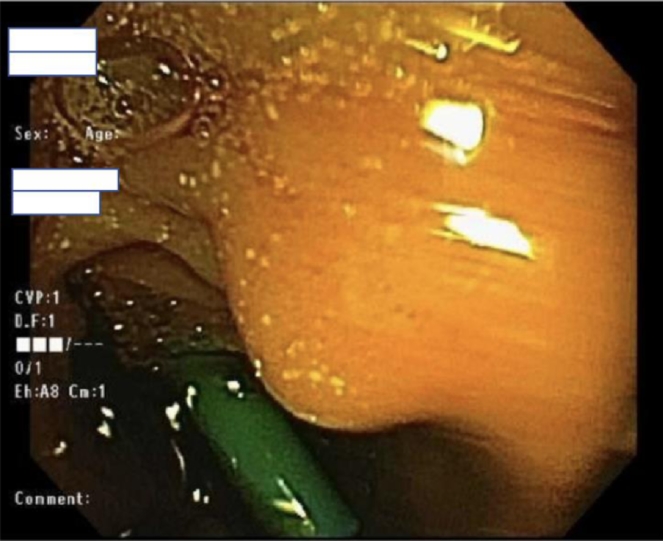

Fig. 6.

(A) A photograph during ERCP after performing sphincterotomy. (B) A photograph during ERCP after common bile duct stent placement.